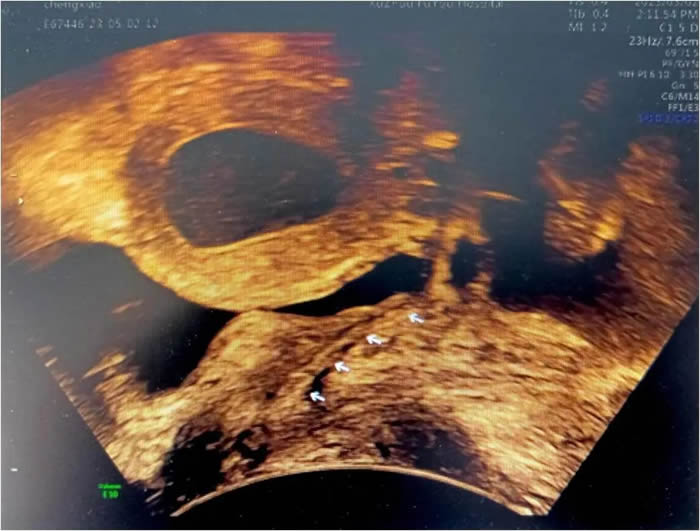

小玲(化名)13歲,到徐州市婦幼保健院就診時(shí),周期性腹痛已持續(xù)一年之久,不僅影響了孩子的學(xué)業(yè)、整個(gè)家庭也陷入了無限的困境。經(jīng)各項(xiàng)檢查發(fā)現(xiàn),小玲患有先天梗阻性生殖道發(fā)育異常,先天性無陰道和條索狀宮頸。雖然如此,小玲的子宮卻發(fā)育良好,所以每次月經(jīng)來潮時(shí),經(jīng)血無法正常排出,只能通過輸卵管逆流到盆腔,導(dǎo)致難以忍受的腹痛。小玲也曾在父母的陪同下到國(guó)內(nèi)多家大醫(yī)院就診,給出的治療方案均是切除子宮體,等待時(shí)機(jī)做二期陰道成形手術(shù),這對(duì)于一個(gè)13歲的女孩,還有父母來說是難以接受的。

早在進(jìn)行前期檢查時(shí),李教授就發(fā)現(xiàn)小玲一側(cè)輸卵管因經(jīng)血逆流造成嚴(yán)重積水傘端封閉,已失去了保留價(jià)值。如果能將積水的輸卵管休整后移植到子宮下端代替宮頸管,便能變廢為寶。但國(guó)內(nèi)、外關(guān)于先天性陰道、宮頸發(fā)育異常的Ⅱ型陰道閉鎖保留子宮的手術(shù)成功案例十分罕見,可參考的資料更是少之又少。國(guó)內(nèi)、外文獻(xiàn)檢索亦未見有使用輸卵管代替宮頸管的案例報(bào)道,也是李桂林教授團(tuán)隊(duì)在醫(yī)學(xué)未知領(lǐng)域的又一次“創(chuàng)新之旅”。